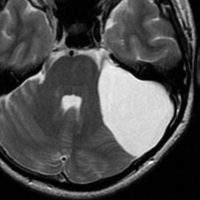

最も多いタイプで50%くらいです。7歳の子に偶然発見された右シルビウス裂のくも膜のう胞です。大きいのですがこの程度では治療の必要はありません。シルビウス裂のくも膜のう胞は最も多いものです。